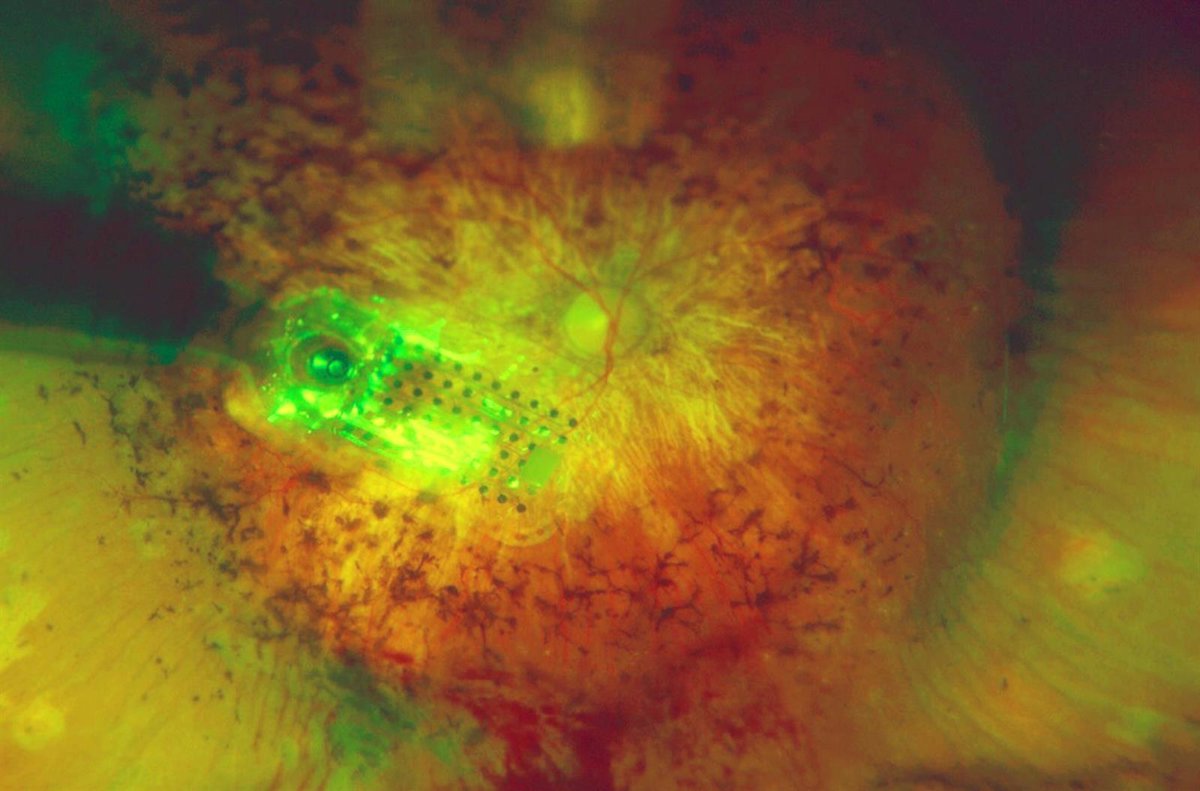

Un momento de la intervención para el implante del ojo biónico

EUROPA PRESS/HOSPITAL LA ARRUZAFA